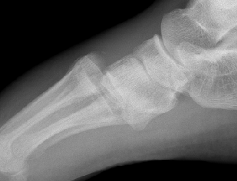

X-ray

AP / Assess medial column

Internal Oblique 30o / Assess lateral column

1. Diastasis of the intermetatarsal gap between the 1st and 2nd metatarsals

2. Widening of the space between the medial cuneiform and base of 2nd metatarsal

3. Second metatarsal Fleck sign - avulsion of Lisfranc ligament from base of 2nd metatarsal

4. Widening of inter-cuneiform distance

- medial border 4th metatarsal aligns with medial border of the cuboid (oblique view)